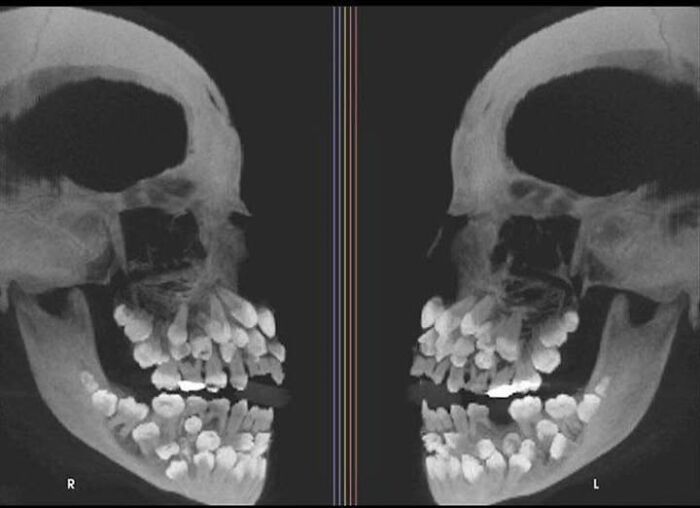

Röntgen pacienta s hyperdonciou, teda stavom, pri ktorom má viac zubov než je bežné, pričom dospelí majú zvyčajne 32 zubov a táto osoba ich mala až 81